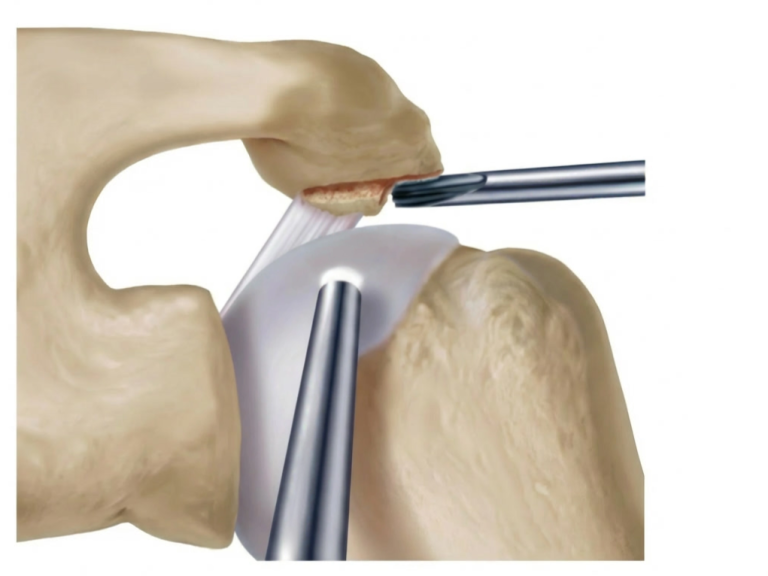

Naht und Refixation

• Verwendung von Fadenankern (Suture Anchors), die im Humeruskopf eingebracht werden. Die Sehne wird mit Fäden durchstochen und zur Knochenoberfläche zurückgeführt.

• Single-Row-Technik: Eine Reihe von Ankern entlang des Footprints.

• Double-Row-Technik: Zwei Reihen für breitere Kontaktfläche (höhere Stabilität).

• Suture-Bridge-Technik: Verbindung beider Reihen